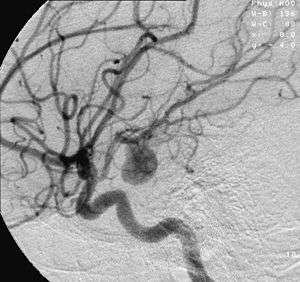

Angiography of an aneurysm in a cerebral artery. The aneurysm is the bean-shaped gray blob in the center of the image. | |